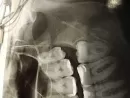

Растёт зуб мудрости, боль, десна опухла. Обратилась на прием к врачу, он сказал делать операцию под общим наркозом, так как тяжелый случай.

Сделала панорамный снимок, сказали зубы мудрости удалять с обеих сторон. Срочно отправляют на операцию.